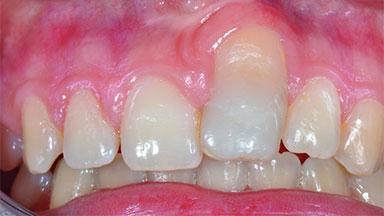

Replacement of an Ankylosed Central Incisor with a Gingival Recession: Tooth Extraction with Socket Grafting and Late Implant Placement with Simultaneous Contour Augmentation